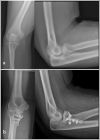

a) Displaced anteromedial fracture of the coronoid b) Stable fixation permitting early range of motion exercises.